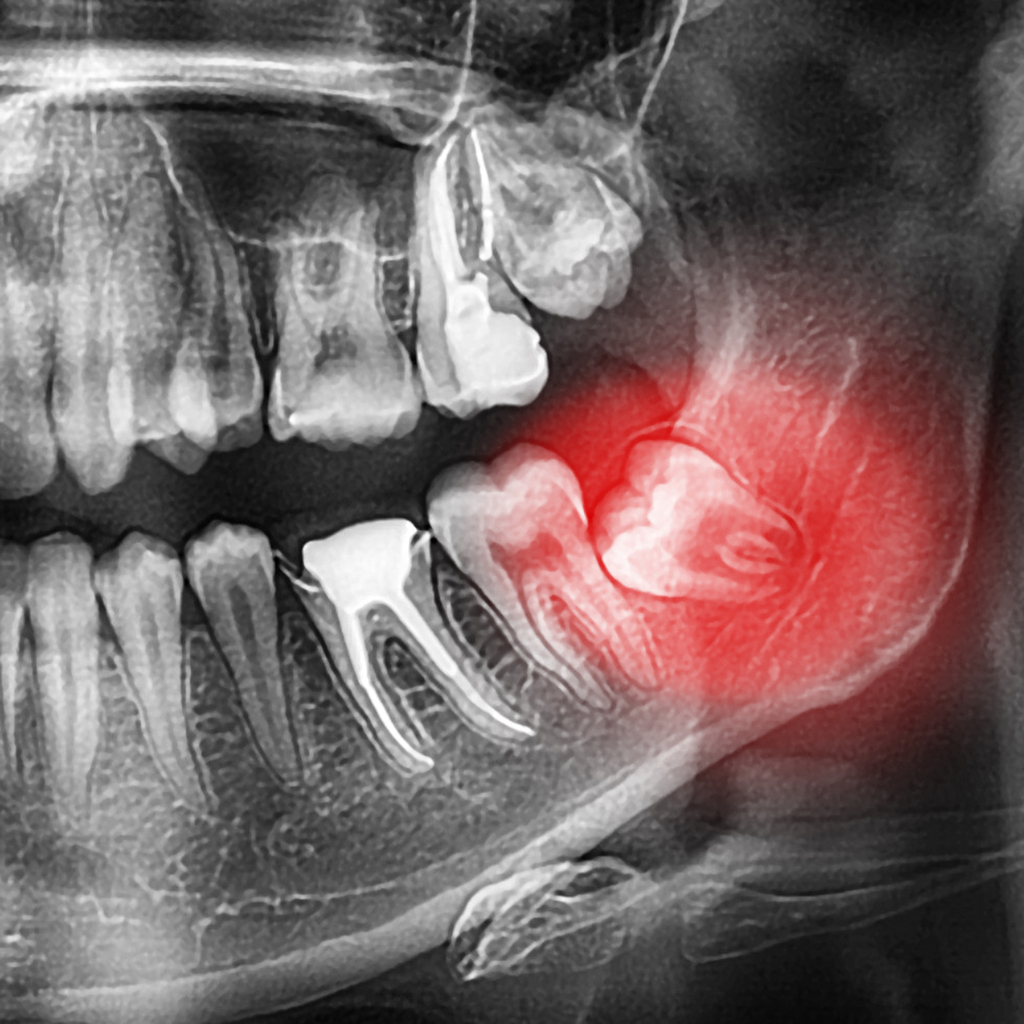

- X-ray

Once your dentist has recommended wisdom teeth removal for you, the next step is taking an x-ray. This will help determine the shape and position of your teeth and will let your dentist know who will perform the procedure.